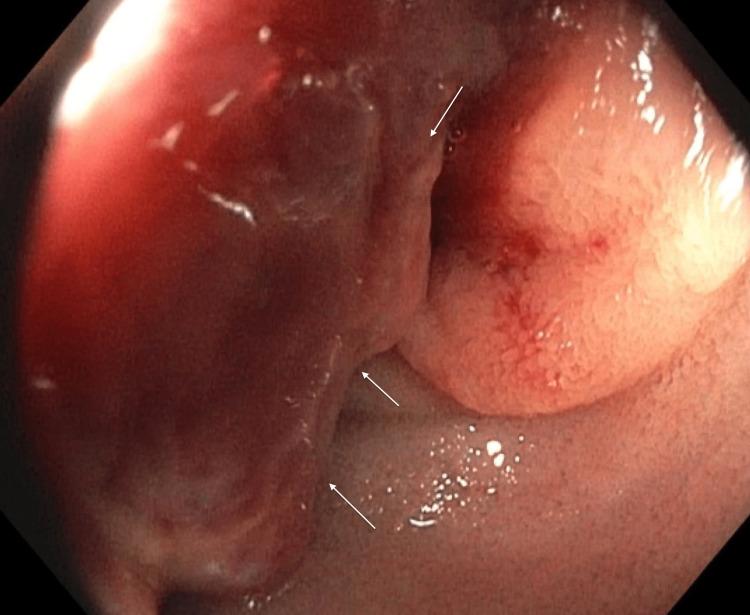

Renal cell carcinoma (RCC) most commonly metastasizes to the lungs, and it is uncommon for RCC to metastasize to the small bowel. Small bowel metastasis commonly presents with gastrointestinal (GI) bleeding. In rare cases, a metastatic small bowel mass can serve as a lead point for intussusception. In this report, we present the case of a male patient whose chief complaint was melena. The patient denied any abdominal pain or nausea. Investigation with push enteroscopy revealed a jejunal mass, and further evaluation with CT showed small bowel intussusception. The patient subsequently underwent small bowel resection and anastomosis. Histopathology confirmed that the jejunal mass was metastatic RCC. We present this case in order to showcase the utility of push enteroscopy in the diagnosis of small bowel metastasis in RCC.

摘要

肾细胞癌(RCC)最常转移至肺部,而RCC转移至小肠并不常见。小肠转移通常表现为胃肠道(GI)出血。在罕见情况下,转移性小肠肿块可作为肠套叠的起始点。在本报告中,我们介绍了一名以黑便为主诉的男性患者。患者否认有任何腹痛或恶心症状。推进式小肠镜检查发现空肠有肿块,CT进一步评估显示小肠套叠。该患者随后接受了小肠切除和吻合术。组织病理学证实空肠肿块为转移性RCC。我们展示此病例是为了说明推进式小肠镜在诊断RCC小肠转移中的作用。